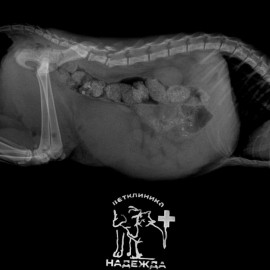

У кошечки была травма, покусана собакой в поясничной области позвоночника. При обращении в клинику отмечались жалобы на слабость тазовых конечностей, шаткая походка. После проведения рентгенологического исследования поставлен диагноз - перелом позвоночника на уровне L6-L7. Была проведена операция - остеосинтез позвоночника L6, спондилодез позвоночника на уровне L5-L7.

Снимок 1 до операции.